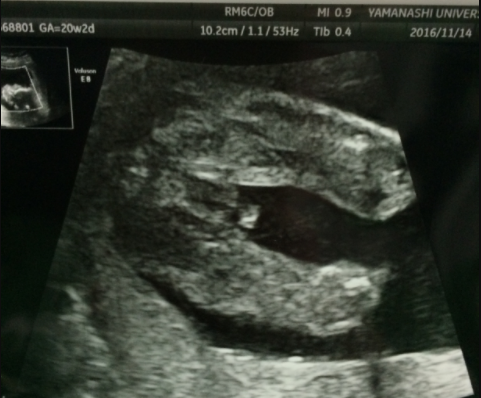

20週2日(20w2d)のエコー写真

20週2日(20w2d・女の子)|ナオコ1213 さん(38歳)

エコー写真撮影時のエピソード:

前回の検診では女の子と判明しました♡次回の検診ではお顔を見せてねーと話しかけていましたが、恥ずかしいのかお顔を見せてくれませんでした^ ^

良く動く子だねーと先生にも言われるほど元気な子で、現在7ヶ月ですが、逆子ちゃんでへその緒も首に巻いた状態です